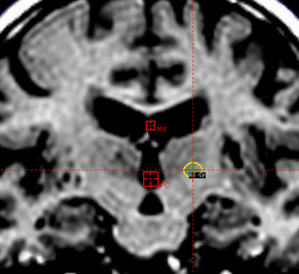

Enhanced visibility of relevant anatomy augments essential accuracy for treating functional indications